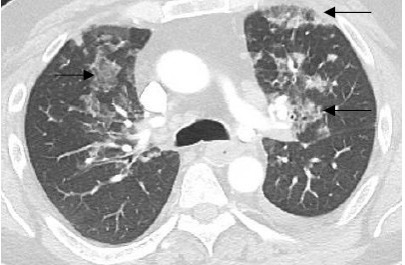

Diagnostic Testing. The patient’s chest x-ray (CXR; Figure 1) and computed tomography angiography (CTA; Figure 2) confirmed the presence of diffuse infiltrates across both lungs, and mediastinal and perihilar adenopathy.

Fig. 2. Transverse view of chest CTA illustrating multiple areas of ground glass consolidation (black arrows).

Previous CXR from the patients’ past hospitalizations indicated no previous pulmonary infiltration. Further laboratory studies revealed a white blood cell count of 13,700/µL (normal range: 4500 - 11,000/ µL) with an eosinophilic predominance of 9.8% (normal range: 1-4%).